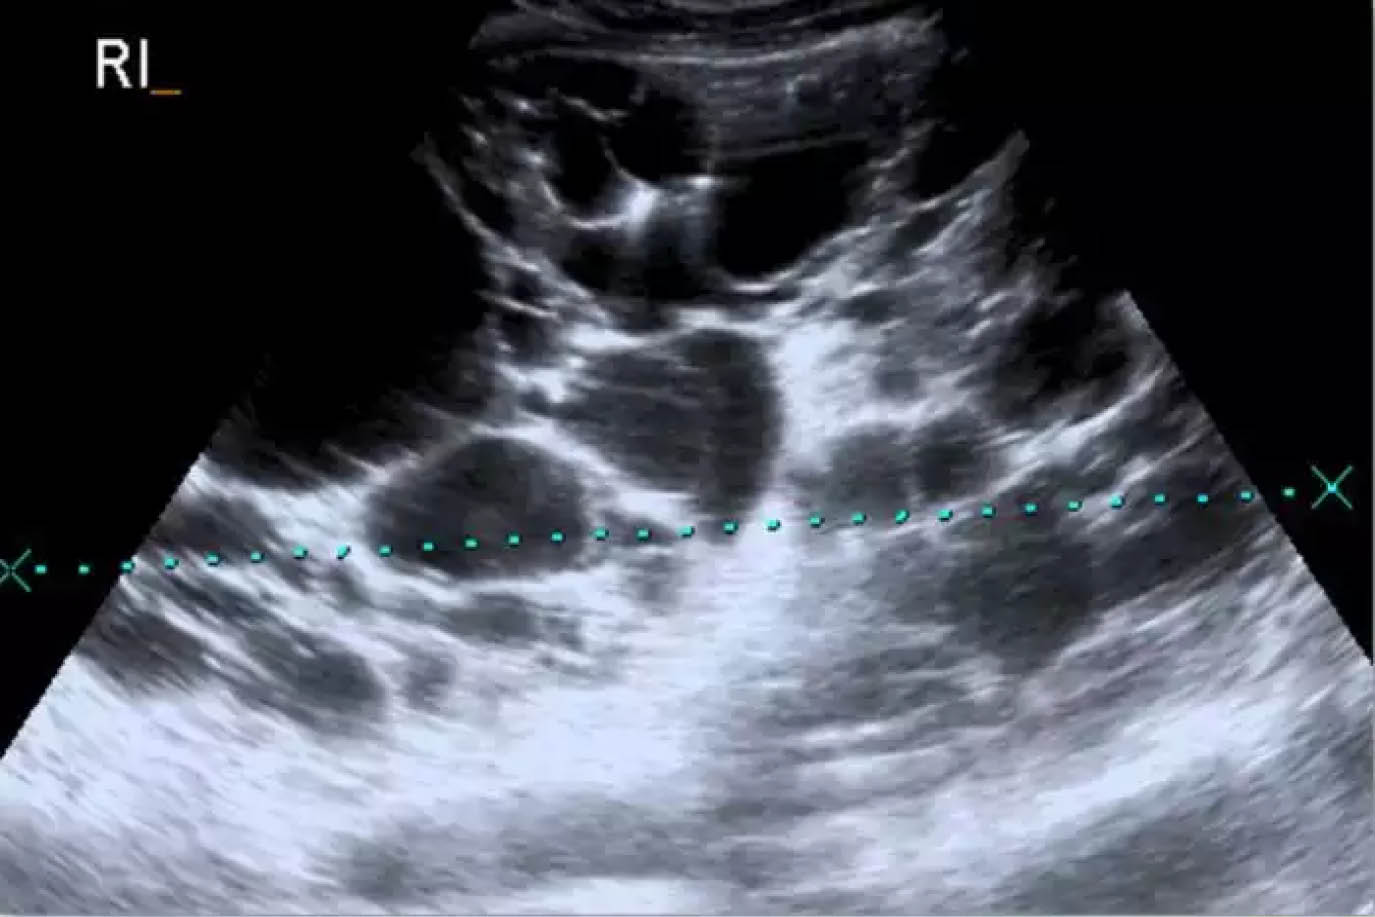

La enfermedad renal poliquística autosómica dominante (ADPKD), la enfermedad renal poliquística autosómica recesiva (ARPKD) y el riñón displásico multicístico presentan características distintivas en la ecografía neonatal.

2. Enfermedad renal poliquística autosómica recesiva (ARPKD):

En la ARPKD, los riñones suelen estar agrandados y presentan una ecogenicidad aumentada con una pobre diferenciación corticomedular. Los quistes son generalmente pequeños y numerosos, distribuidos en la corteza y la médula, lo que puede dar una apariencia de «sal y pimienta» en la ecografía. Esta condición puede estar asociada con oligohidramnios y características de síndrome de Potter debido a la compresión fetal.[4]

La ecografía es una herramienta crucial para diferenciar estas condiciones en neonatos, permitiendo una evaluación detallada de la estructura y la ecogenicidad renal, así como la identificación de quistes y su distribución.